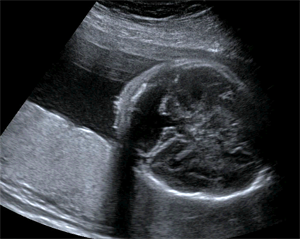

Pediatric cranial sonogram.

Pediatric Imaging

Dramatic advances in imaging technologies are improving the ability of pediatric radiologists to diagnose complex cases in children. For all imaging of children at UCSF we pay special attention to ensuring that protocols are pediatric specific and that all imaging studies are interpreted by radiologists who are specially trained in pediatric anatomy and pathology. UCSF ascribes to the policy of “imaging gently“[1] in the imaging of children, and the use of ultrasound is an important tool in achieving that goal.

UCSF’s ultrasound subspecialty has world-renowned experts in prenatal ultrasound imaging as well as for children and babies. Our expert staff includes specialists in prenatal imaging of congenital anomalies and fetal therapy.